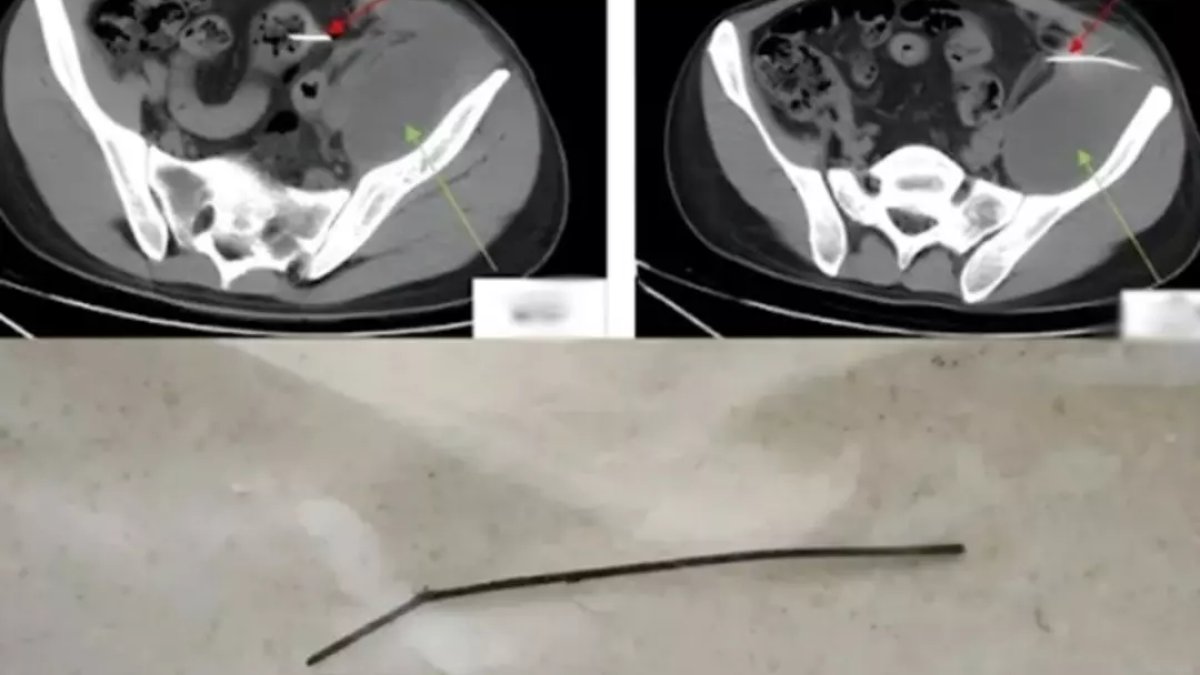

Doktorlar gördükleri karşısında şoke oldu: Günlerdir tuvalete çıkamıyordu